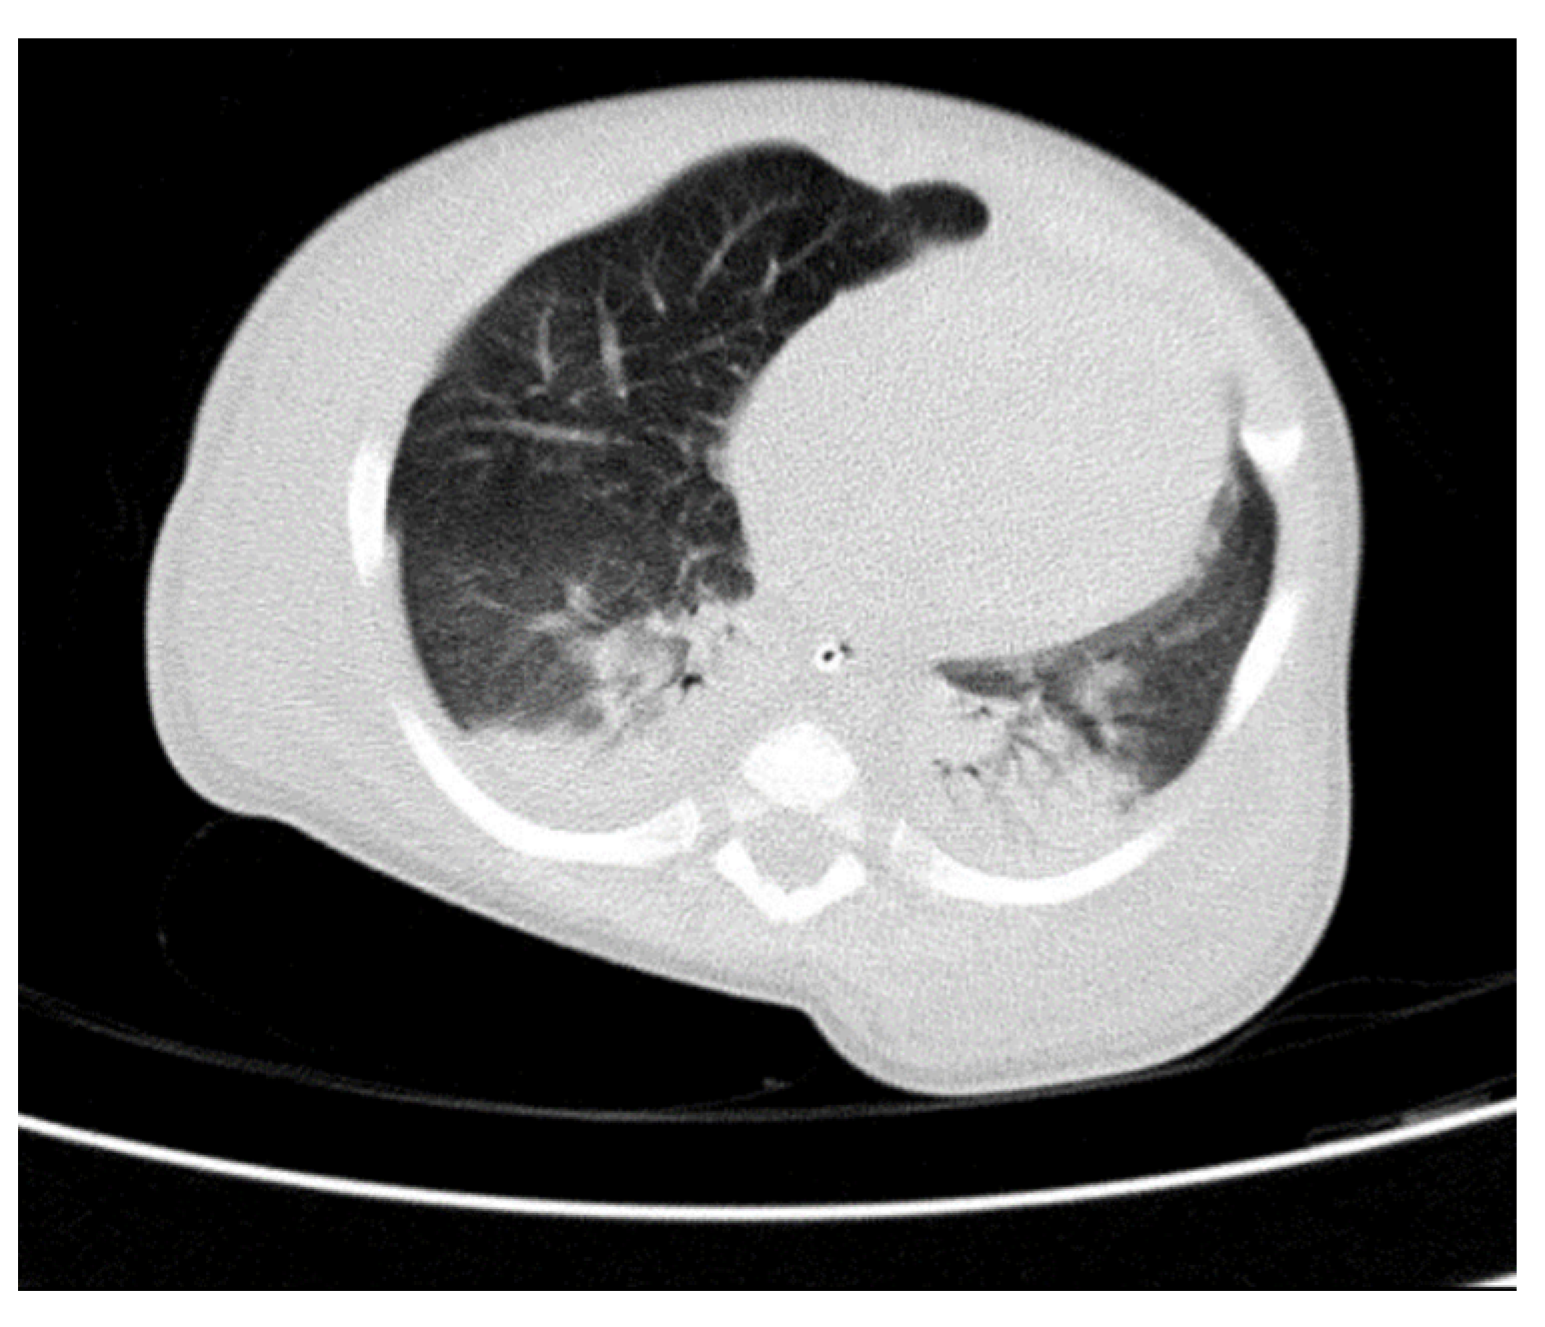

Through thoracic CT, we found SVC with a diameter of 15 mm (Figure 1), a venous collector with a 12 mm in diameter connected to the SVC and identified at the level of a plane passing through the middle of the left superior pulmonary lobe (Figure 2). The venous structure continues superiorly with the left brachiocephalic venous trunk, which was dilated up to 12 mm (Figure 3) and inferiorly with a left pulmonary vein. The pulmonary trunk appeared shorter, with a diameter of 6 mm, right pulmonary artery = 5.4 mm and left pulmonary artery = 5.6 mm (Figure 4 and Figure 5). We have identified traits of pulmonary consolidation (Figure 6).

Figure 6.

Pulmonary consolidation.